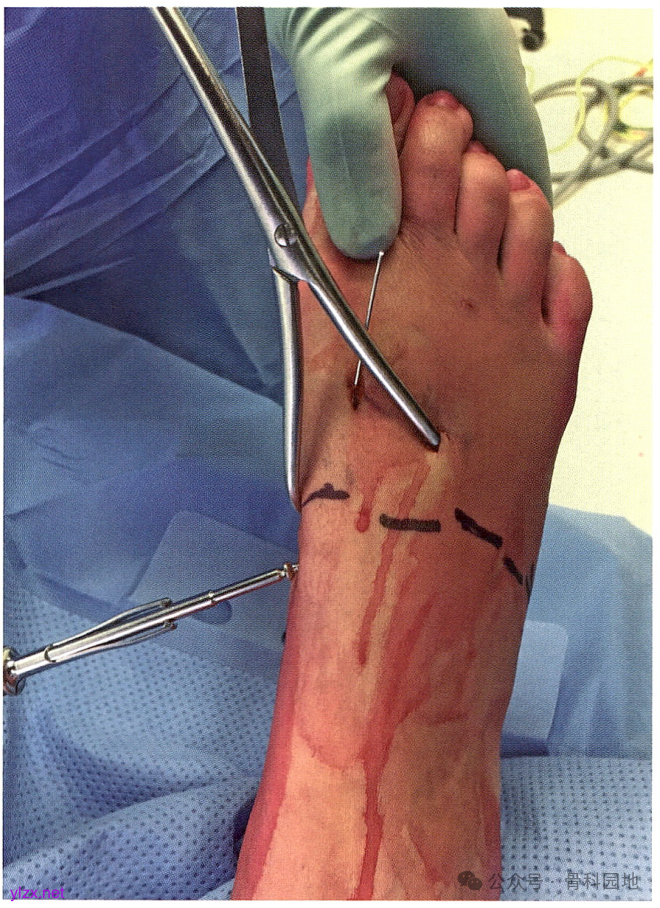

术前计划:第2 TMT 关节复位方向,螺钉和克氏针置入方向。只有在第 4/第5 TMT 关节不稳定时才使用克氏针固定。

体位:Lisfranc 损伤经皮固定的经典手术体位。本例为左足损伤。在同侧髋部下方垫高,将患足位置调整合适。

然后用点式复位(Weber)钳和手法复位第3TMT 关节。待第3TMT 关节复位后,经关节钻人1枚克氏针。